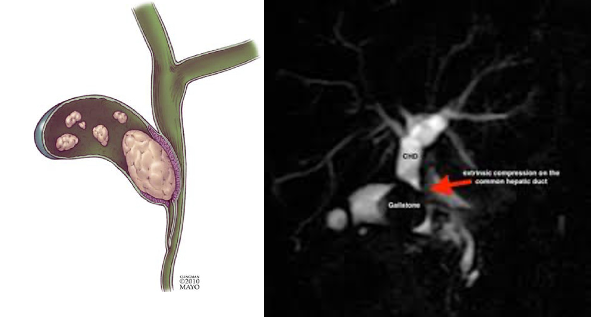

Mirizzi's syndrome

• 정의: 담낭관이나 담낭 경부에 박힌 담석이 총담관(CBD)을 외부에서 압박하여 총담관 폐쇄와 황달을 유발하는 드문 합병증

• 진단: 초음파, ERCP, MRCP로 총담관의 외인성 압박을 확인

• 치료: 담낭관, 담낭, 박힌 담석을 제거하는 수술이 필요하며, 수술 중 총담관 손상을 피하기 위해 수술 전 진단이 중요